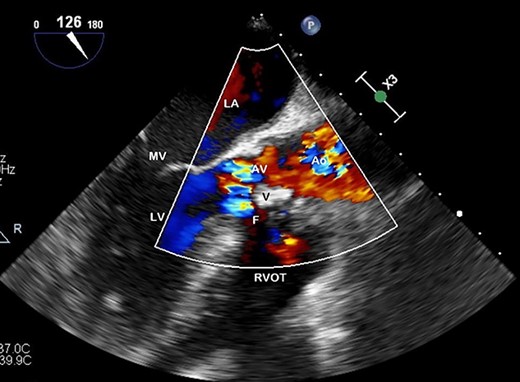

The patient developed complete heart block, and subsequently, Torsades de Pointe, requiring an isoprenaline infusion, pacing via a temporary venous pacing system (and removed post-operatively) and urgent coiling of a large 4.8 × 2.5 cm right middle cerebral artery mycotic aneurysm 1 day prior to his redo-valve surgery. A repeat TOE demonstrated severe aortic regurgitation, prosthetic valve abscess, dehiscing and fistulizing from the aortic root to right ventricle (RV) on colour-flow doppler (Fig. 3). Proceeding to surgery, on inspection of the aortic root—findings confirmed a largely destroyed AV, multiple valvular vegetations and fistulization from the aortic root just below his right coronary cusp to his RV. A redo-sternotomy was performed, central cannulation was utilized—cross-clamp and bypass times were 89 and 141 minutes, respectively. Abscess debridement and an AVR (#23 Carpentier-Edwards Perimount magna-ease) were undertaken, with the fistula closed with the valve sutures, and a post-operative TOE confirmed no persisting fistula or peri or para-valvular leak around the new AV prosthesis, indicating significant improvement. He was referred for counselling with the Drug and Alcohol Service during his admission with extensive planned follow-up to maintain abstinence from IV drug use. The patient remained in sinus rhythm, completed 6 weeks of antimicrobial therapy and discharged home with no issues on follow-up.

Preoperative TOE, long axis with colour flow highlighting the vegetation (V) obstructing flow through the AV and the fistula (F) which has developed from left ventricular outflow tract to RVOT.